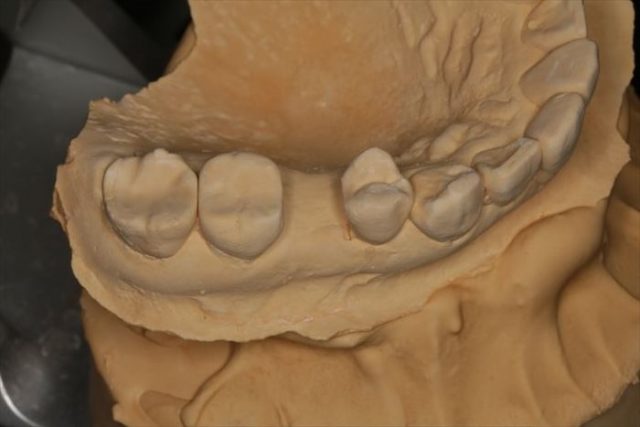

上下歯列の型取りとフェイスボウトランスファーを行い、上顎歯列と顎関節の関係を記録します。

フェイスボウの記録を利用して、咬合器に上下歯列模型をマウントしました。

模型上でシミュレーションしてサージカルステント(ドリルガイド)を作成し、準備は完了です。